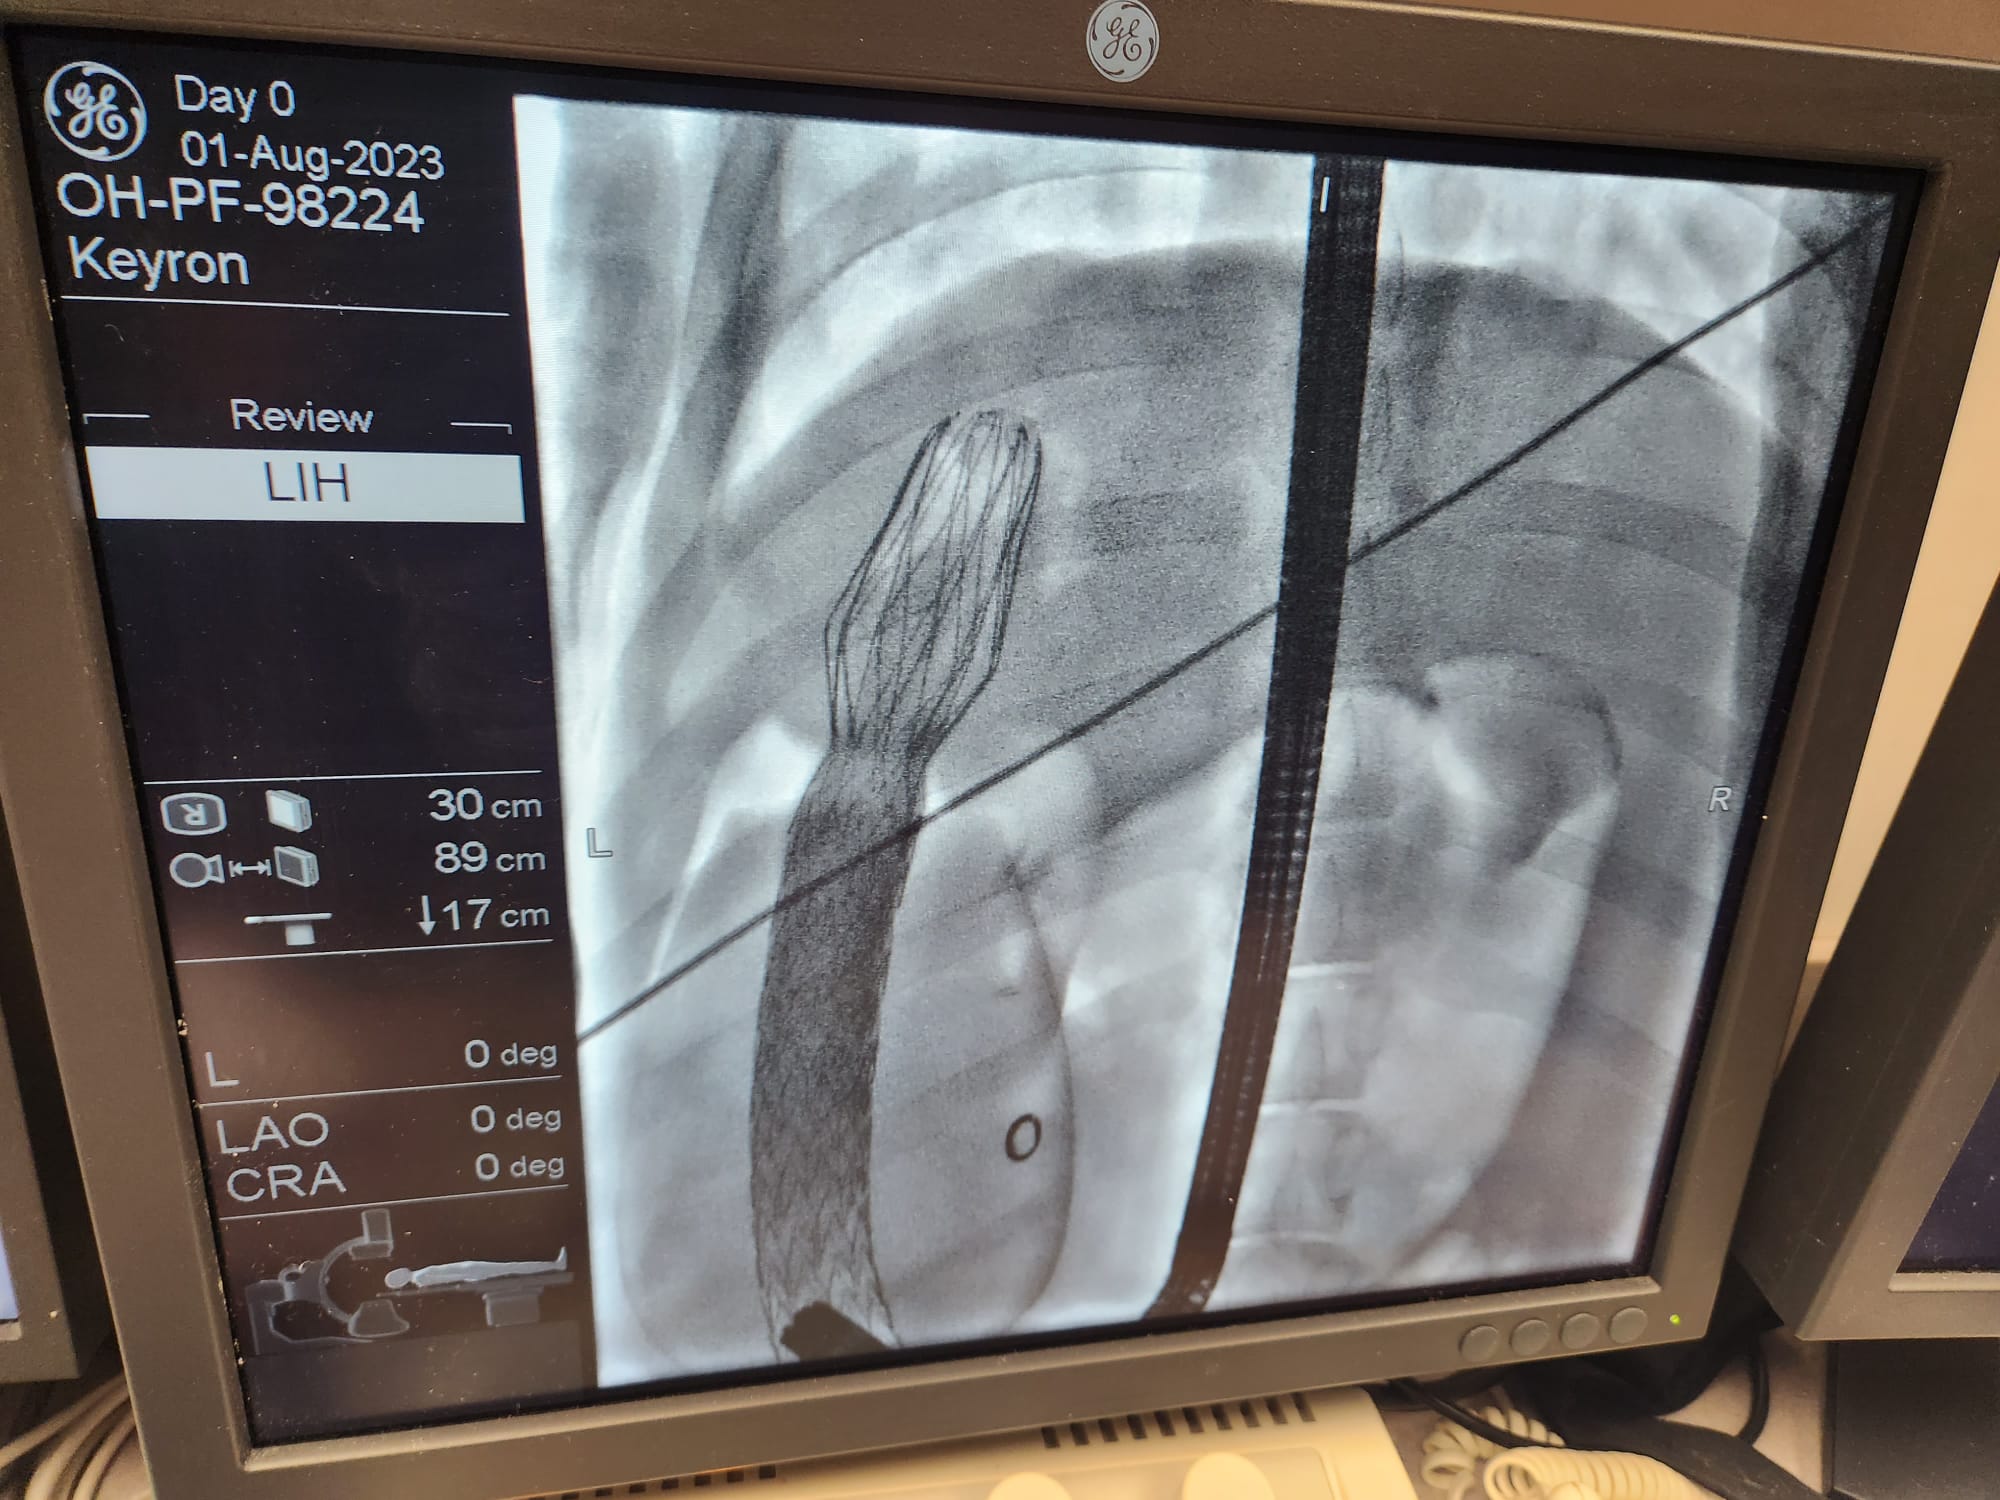

Long-Term Safety & Efficacy in Swine

Proven Long-Term Safety

Proven Correct and Stable Long-Term Positioning